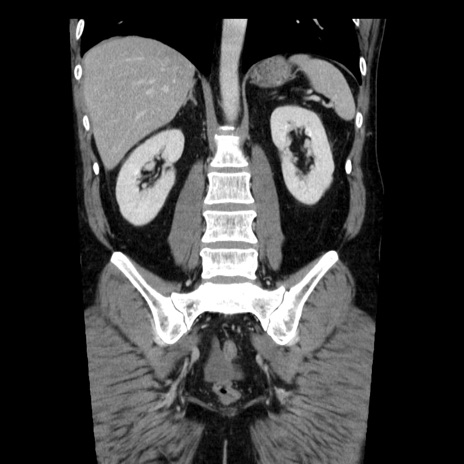

症例29(冠状断像)

【症例】40歳代男性

【現病歴】2日前から胃痛あり。徐々に周期的な激痛に変化した。本日になっても激痛があるため受診。

【身体所見】意識清明、BT 38-39℃台あり、腹部:膨満、やや硬、右下腹部に圧痛あり。

【データ】WBC 8500、CRP 23.26